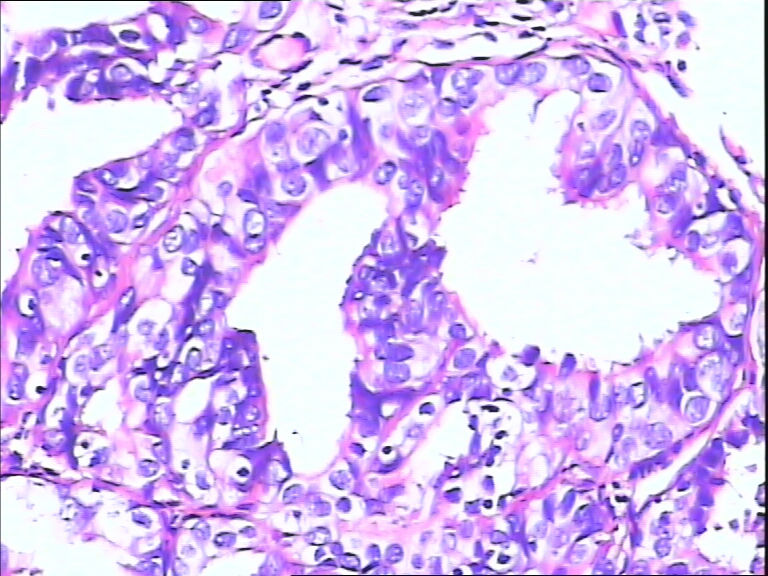

女,43y

左输卵管积液

输卵管长4.5cm;直径:0.8cm

• 请教:输卵管!图3

图3

输卵管增生性上皮病变。

慢性炎伴上皮增生

良性,炎症改变

考虑炎症